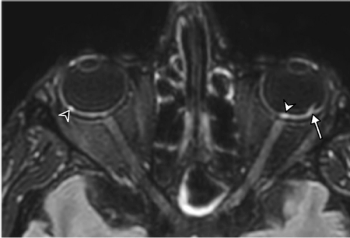

First brain MRI findings reveal dangerous COVID-19-related optical findings.